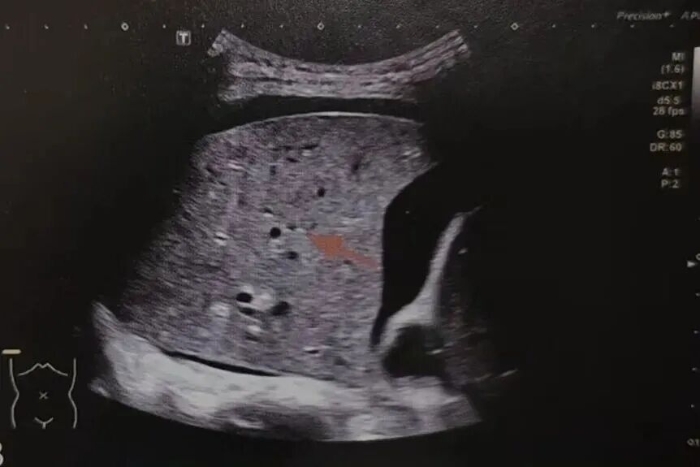

B线: 从胸膜发出、像激光束一样垂直向下延伸的线。B线增多,提示肺里有间质水肿或炎症,也就是我们常说的“肺水多了” 。

新生儿呼吸窘迫综合征超声表现为双肺弥漫分布的密集B线,双肺近胸膜下小片状肺实变。